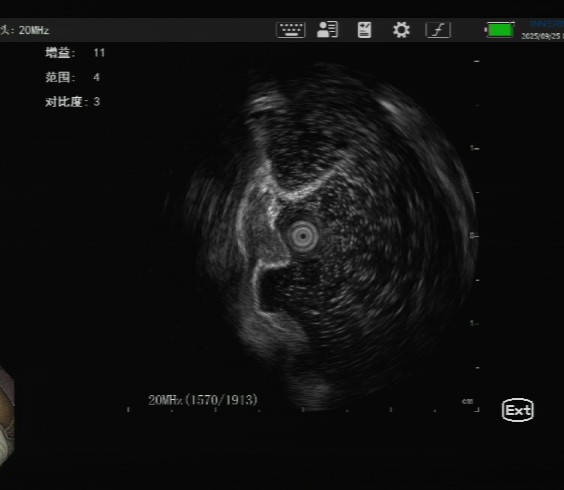

精准评估:肿瘤“间谍地图”——超声内镜

消化内科团队为其行进一步超声内镜评估显示,病灶尚未侵及肌层,符合内镜下黏膜下剥离术(ESD)指征。